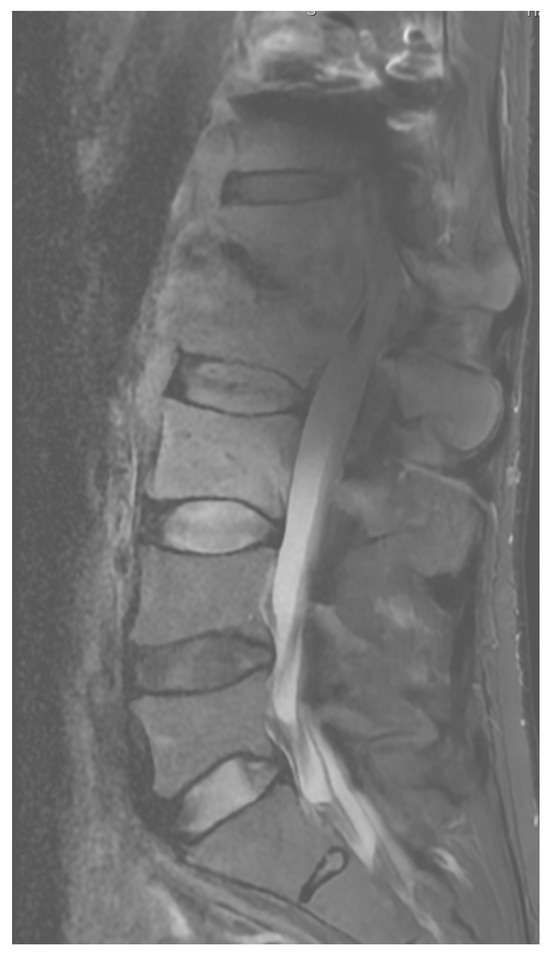

Patient Background: A 70-year-old male patient with a history of diabetes and chronic renal failure was scheduled for surgical treatment of discopathy at the L3/L4 level (Figure 6). The patient underwent microdiscectomy using a minimally invasive access retractor Spotlight (Johnson and Johnson, New Brunswick, NJ, USA).

Figure 6. Pre-operative T2 sagittal MRI image at the L3/L4.